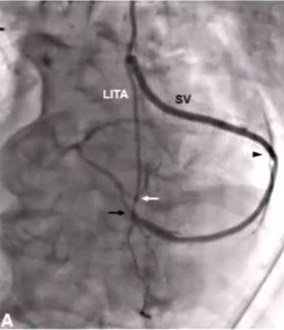

Can a Single ITA Composite Graft Adequately Supply the Heart?